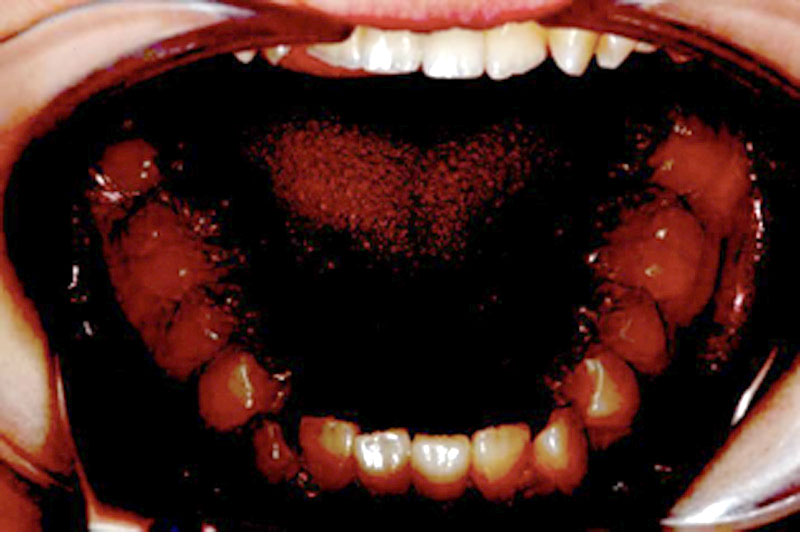

CASE 3 13歳 男

| 悩み | 上下の前歯の歯並びを治したい。 |

|---|---|

| 抜歯 | 上下小臼歯4本 |

| 装置 | マルチブラケット(表)、トランスパラタルアーチ、ヘッドギア(夜間) |

| 内容 | 前歯にガタガタがあり骨格的な顎の幅が不足していたため抜歯を選択し、成長期の顎の成長を利用して奥歯のかみ合わせを整える治療を行った。奥歯のかみ合わせが改善され、見た目もきれいになった。 |

| 期間 | 3年2ヶ月 |

| リスク | う蝕、歯周病、歯根吸収、口内炎 |

| 費用 | 70万円(調整料は含みません) |